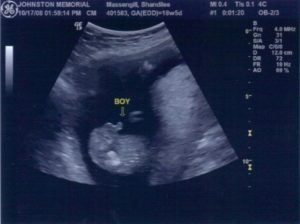

На УЗИ, которое проводят на 15-й неделе беременности будущей матери видно, как активно двигает малыш ручками, ножками. Этот срок характеризуется усиленным развитием мышечной системы.

При удачном расположении плода врач-сонолог может сказать пол ожидаемого малыша. УЗИ на 15-й неделе позволяет проследить за активностью ребенка.

На экране же малыш выглядит длиною около пальца. Если выполняют 3D УЗИ, то на экране видно недовольство крохи, которое проявляется при нажатии на живот датчиком. Ребенок может хмурить бровки, хвататься за пуповину, активнее двигаться.